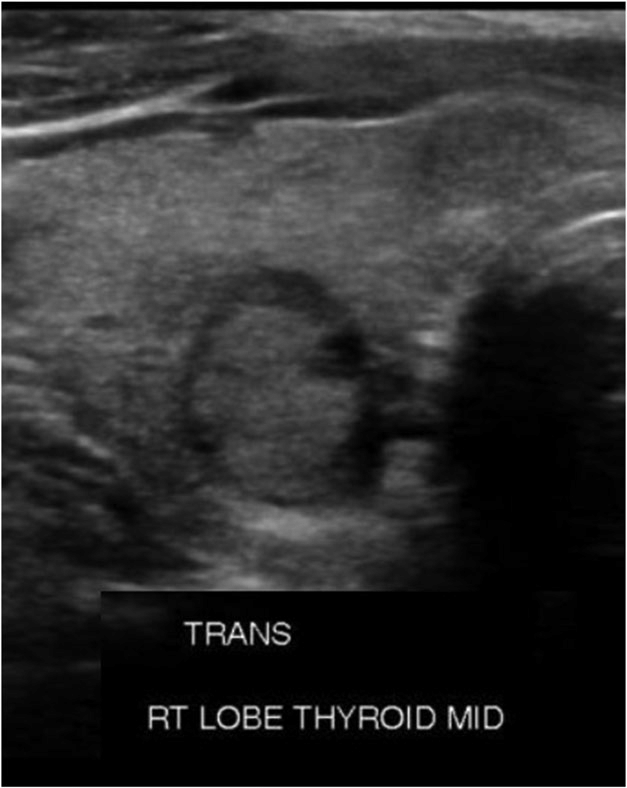

고형(solid): 초음파를 보면 액체 여부를 어느 정도 구별할 수 있는데 딱딱하게 보이는 구조물을 말합니다. 아래 사진은 알아보기 쉽게 액체와 고체부분이 섞여있는것을 가지고있는데요, 검은부분이 액체이고 그안에 밝은부분이 고체부분입니다.

저에코(hypoechogenic n odule) : 초음파에서 다른 조직에 비해 더 어두워 보이는 병변을 말합니다.